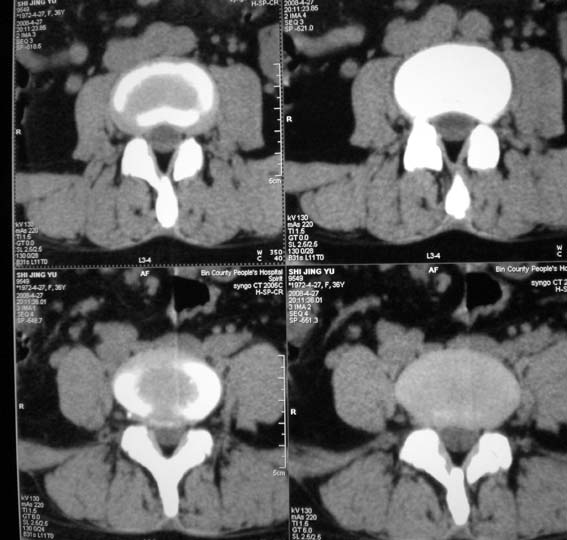

女,36岁,腰痛多年,坐久后,起身疼痛难忍。

腰4/5椎间盘轻度膨出,腰5/骶1椎间盘突出(右旁中央型)伴局部椎间盘钙化。

后纵韧带钙化

腰4~5椎间盘膨出并突出,腰5~骶1椎间盘突出(右外侧型)伴局部椎间盘钙化。